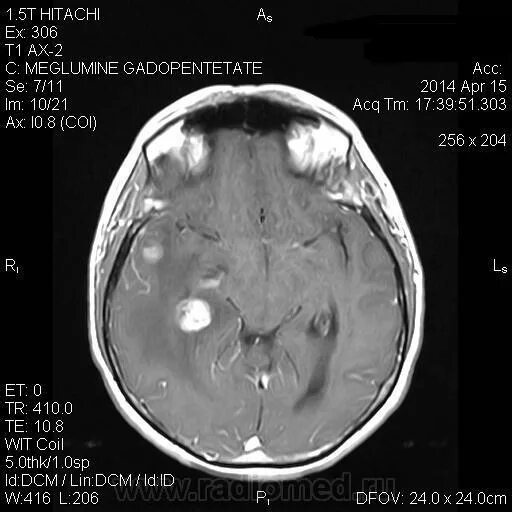

Рмж метастазы в легкие